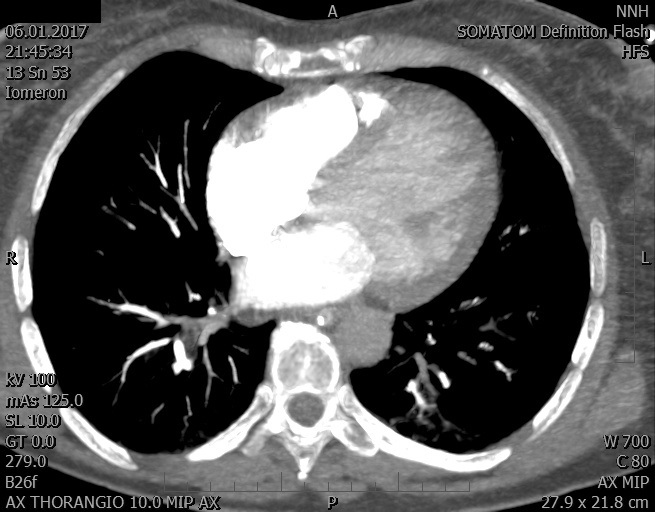

Video 1 - Akutní koronarografie prokázala normální nález na věnčitých tepnách s výjimkou suspekce na lehký spasmus na pravé koronární tepně.Echokardiograficky byla zjištěna těžká dysfunkce dilatované levé komory s nezvětšenou pravou komorou (video 2).

Video 2 - Echokardiograficky byla zjištěna těžká dysfunkce dilatační levé komory s nezvětšenou pravou komorou.Pro nejasnou příčinu zástavy jsme provedli i vyšetření výpočetní tomografií (CT), které vyloučilo plicní embolizaci (série 1 - soubory na konci článku). V den přijetí při přetrvávající oběhové nestabilitě byla nemocná opakovaně defibrilována pro fibrilaci komor se stabilizací rytmu po podání amiodaronu a mesocainu. Dle hemodynamických měření se jednalo o těžký kombinovaný šok. Vstupní laboratorní vyšetření bylo bez větších pozoruhodností. Posléze jsme doplnili anamnézu od příbuzných a zjistili, že pacientka užila do dvou hodin před srdeční zástavou první tabletu amoxicilinu na lehký respirační infekt. Při nevýtěžnosti vstupních vyšetření a nových anamnestických informacích jsme doplnili 14 hodin po kolapsu vyšetření koncentrace tryptázy v séru, která byla extrémně zvýšena (tabulka 2), což nás vedlo k podezření na anafylaxi.